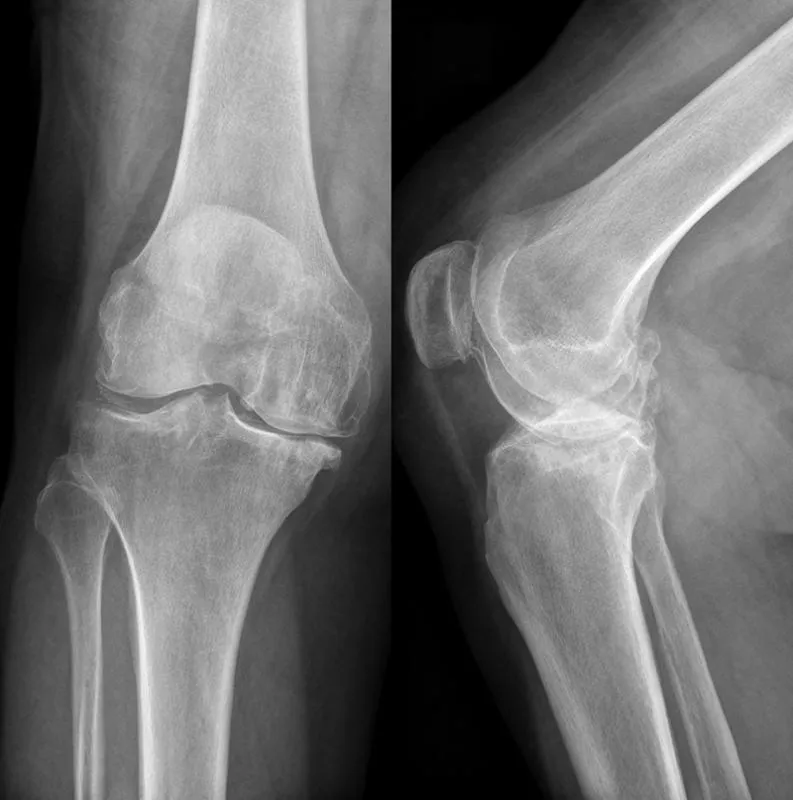

Он позволяет полностью восстановить костную ткань, в том числе, после крупных осколочных и пулевых ранений, что более чем актуально сегодня.

Гель для заполнения костных дефектов, не только удобен для работы хирурга, но и обеспечивает более глубокое проникновение в скрытые полости, плотный контакт с поврежденными тканями.

Разработка может использоваться, к примеру, при операциях на костных тканях челюстно-лицевой области, для заполнения дефектов костной и хрящевой тканей в стоматологии и хирурги и так далее.